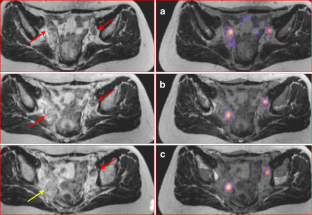

Fig. 4